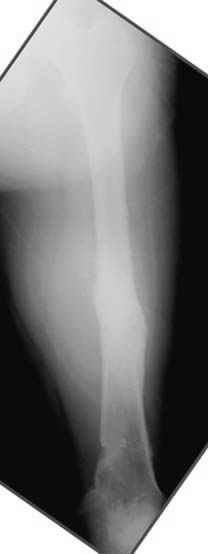

Если, например, доводится лечить больных с псевдартрозами шейки бедра, то надобность есть, и приходится. См. приложение.

Несколько снимков из моей коллекции, чтобы разьяснить, почему мы до сих пор делаем различные варианты остеотомии.

На рисунке N1 предоперационный план лечения ложного сустава шейки бедра- линия ложного сустава, угол и направление введения импланта, клиновидная остеотомия в градусах и миллиметрах, второй снимок после коррекции, расчет, на сколько удлиняется конечность и размеры импланта;

N3 рисунок окончательный снимок, после операции моя рентгенограмма должен выглядеть примерно как эта картина. На N4 снимке клин перед удалением; N5 послеоперации 3 нед.; N6 окончательная рентгенограмма.

Отправитель: Djoldas Kuldjanov 23 Ноябрь 2004, 18:21

пластическая модель; и коррекция бедра аппаратом Илизарова.